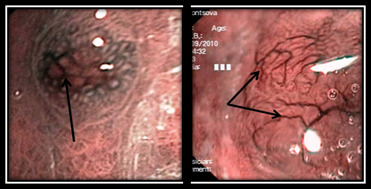

Рис. 1 (а, б). Эндофото. Плосковозвышающаяся форма НЭО желудка

Во всех случаях данная форма НЭО сочеталась с явлениями умеренно выраженной либо выраженной атрофии слизистой оболочки, которые проявлялись в усилении сосудистого рисунка слизистого и подслизистого слоев и истончении слизистого слоя. При осмотре с оптическим увеличением области патологического очага архитектоника слизистой оболочки либо представлена ямочным рисунком соответствующего отдела желудка, где локализуется опухоль, либо соответствует ее гиперпластической перестройке. Последняя определяется удлинением и извитостью ямок слизистой оболочки желудка, увеличением расстояния между ними, а также увеличением ширины и высоты желудочных валиков, при этом сохраняется регулярность ямочного рисунка без формирования участков его деструктуризации (рис. 1а). Изменение архитектоники сосудистого рисунка проявляется в виде появления сети полнокровных извитых сосудов, ограниченной зоной образования, которая более детально визуализируется в режиме NBI. Угловатый рисунок сосудов обусловлен расширением крупных посткапиллярных вен, имеющих звездчатую форму (v. v. stellatae) и локализующихся непосредственно под эпителием слизистой оболочки желудка (рис. 1б).

Полиповидная форма НЭО желудка выявлена у 36 пациентов. Определяется как экзофитное образование полиповидной или бляшковидной формы размером более 5 мм, с разрыхленной гиперемированной поверхностью, плотно-эластичной консистенции. Как и для плосковозвышающейся формы НЭО желудка, патогномоничным признаком является изменение сосудистого рисунка на поверхности образования, проявляющееся полнокровными извитыми сосудами, ограниченными областью патологического очага (рис. 1а). Детально данные изменения визуализируются при осмотре в режиме NBI. В трех случаях изменения сосудистого рисунка при полиповидной форме НЭО были представлены диффузным усилением кровенаполнения внутрислизистых микрососудов с формированием небольших ярких гиперемированных очагов овальной формы от 1 до 4 мм.

Рис. 2 (а, б). Эндофото. Полиповидная форма НЭО желудка

Изменения архитектоники ямочного рисунка на верхушке образования соответствуют эпителиальной злокачественной опухоли, то есть ямочный рисунок в центре участка стерт, по периферии отмечается нарушение регулярности структуры ямочного рисунка. У основания образования ямочный рисунок неизменен и соответствует отделу желудка, в котором локализуется опухоль. Нередко вышеописанные изменения замещены гиперплазией слизистой оболочки, обусловленной гипергастринэмией, с соответствующей гиперпластической перестройкой ямочного рисунка на всей поверхности образования. Достаточно часто при таком типе НЭО желудка на верхушке образования отмечаются зоны повреждения слизистой оболочки — вплоть до кратерообразных изъязвлений (рис. 1б).